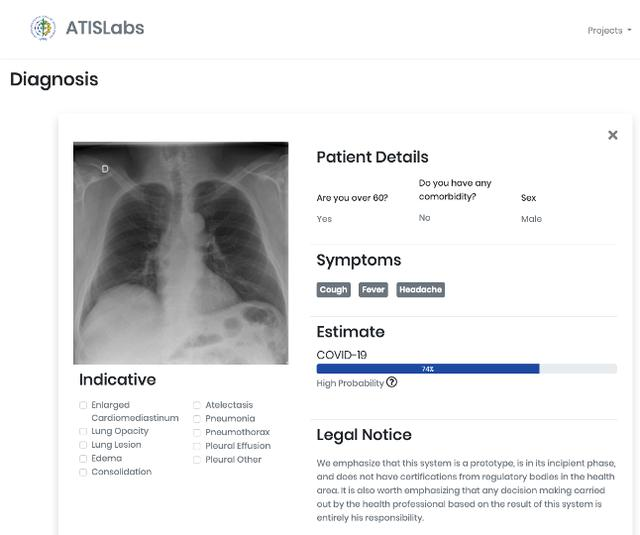

该项目的灵感来源于UFRRJ(里约热内卢联邦大学)开发的X光COVID-19项目。UFRRJ的XRayCovid-19是一个正在开发的项目,在诊断过程中使用人工智能辅助健康系统处理COVID-19。该工具的特点是易用、响应时间快和结果有效性高,我希望将这些特点扩展到本教程第4部分开发的Web应用程序中。下面是诊断结果之一的打印屏幕(使用了Covid-19数据集1图像之一):

乔杜里等人在论文中阐述了该大学开展这项工作的科学依据,论文地址:https://arxiv.org/abs/2003.13145